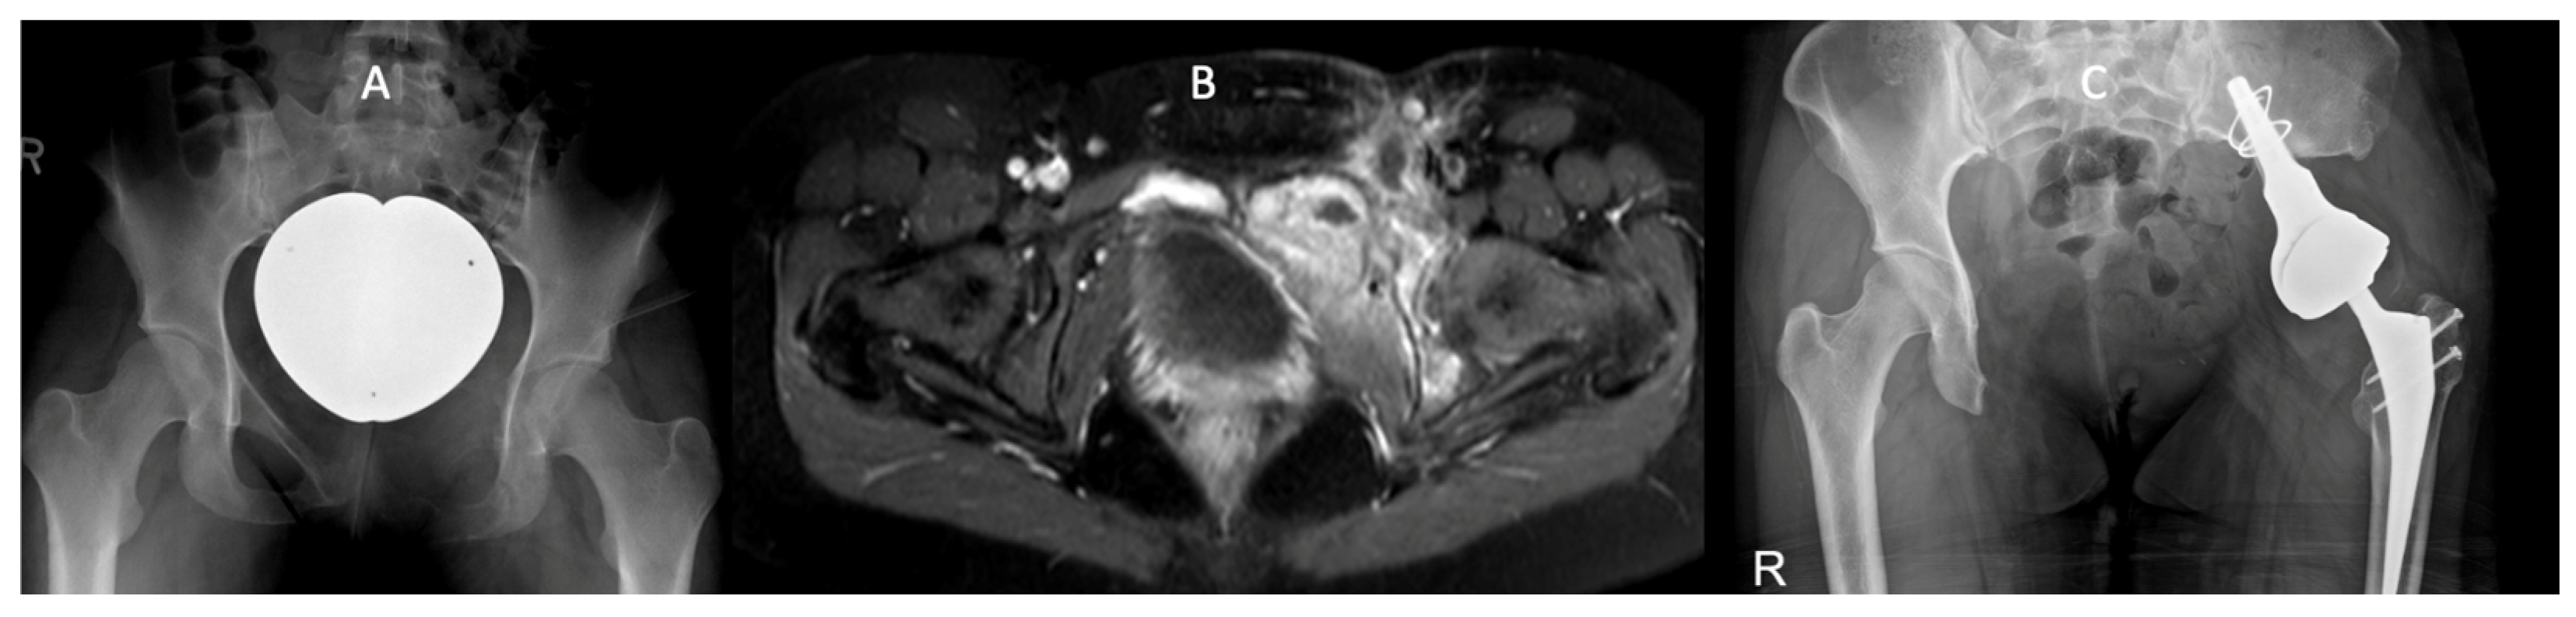

3.3. Example Case